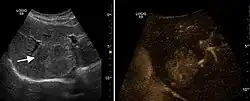

2D ultrasound, Doppler ultrasound and especially CEUS can play an important role in pretherapeutic staging, particularly when sectional imaging investigations (CT, MRI) provide uncertain results or are contraindicated. During the interventional procedure, ultrasound allows guidance of the needle into the tumor. CEUS allows guidance in areas of viable tissue and avoids intratumoral necrotic areas. CEUS also allows assessment of therapeutic effect immediately post-procedure (with the possibility of reintervention in case of partial response) . To accurately assess the effectiveness of treatment it is mandatory to compare the tumor diameter before therapy with the ablation area. The volume of damaged tissue must be higher than the initial tumor volume. CEUS appearance is that of central nonenhanced area showing a peripheral homogeneous hyperenhanced rim due to post-procedure inflammation. 24 hours after the procedure the inflammatory peripheral rim is thinning and the necrotic area appears larger than at the previous examination. Thus, a possible residual tumor may appear more evident. Residual tumor has poorly defined edges, irregular shape, and the tumor diameter is unchanged. Residual tumor tissue is evidenced at the periphery of the tumor as an eccentric area behaving as the original tumor at CEUS examination, with arterial hyperenhancement and portal and late wash-out. Ultrasound examination 24 hours after the procedure, including CEUS, can show apart from the character of the lesion any potential post-intervention complications (e.g. active bleeding).

Local recurrence is defined as recurrence of a hyperenhanced area at tumor periphery in the arterial phase, with portal and late wash-out. Sometimes, especially for HCC treated by alcoholization (PEI) hyperenhanced septa or vessels can be shown inside the lesion.